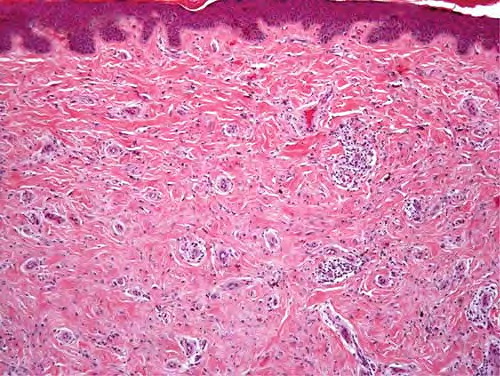

Sclerosing spitz nevus = وحمة سبيتز التصلبية

Unlike ordinary nevi and melanomas, melanocytic cells in Spitz nevi are large—often twice the size of epidermal basal keratinocytes, with prominent mononuclear or multinucleated giant cells in the epidermis and/or dermis . Mitoses, usually few in number, are detected in one-half the cases, whereas atypical mitoses are uncommon in Spitz nevi. In contrast to melanoma, the melanocytic cells in Spitz nevi show progressive maturation with increasing depth, becoming smaller and more similar to ordinary nevomelanocytes, with the overall distribution of cells in the dermis being wedge-shaped, with narrowing of the wedge toward the subcutaneous fat.

Coalescent eosinophilic globules (Kamino bodies), periodic acid-Schiff-positive and diastase-resistant (resembling colloid bodies), have been reported in 60 percent of Spitz nevi. Similar globules may be detected in 2 percent of melanomas and 0.9 percent of typical acquired nevi, but the globules are smaller in size, more difficult to find, single rather than coalescent, and commonly periodic acid-Schiff-negative.

Melanocytic elements are usually arranged in well-circumscribed nests, although there may be permeation of the epidermis by single cells or small groups of cells. In those cases with epidermal nests, artifactual clefts are usually seen above the nests in half the cases, a finding rarely observed in melanoma. The epidermis is usually hyperplastic, with elongated and bulbous pegs and knobs extending into the dermis, although thinning and even ulceration may occur rarely. The dermal inflammatory cell infiltrate may be slight or marked, band-like, and mainly at the base or patchy around blood vessels and/or intermixing with tumor cells. Although melanin was observed in all 13 patients originally described by Spitz, more recent studies have determined that melanin was moderate in 10 percent of cases and heavy in 5 percent.88

Although the bizarre histopathologic features and frequent occurrence of dermal inflammation may cause diagnostic confusion, Spitz nevus usually can be differentiated from melanoma. The histologic features of Spitz nevus in children and adults are similar.